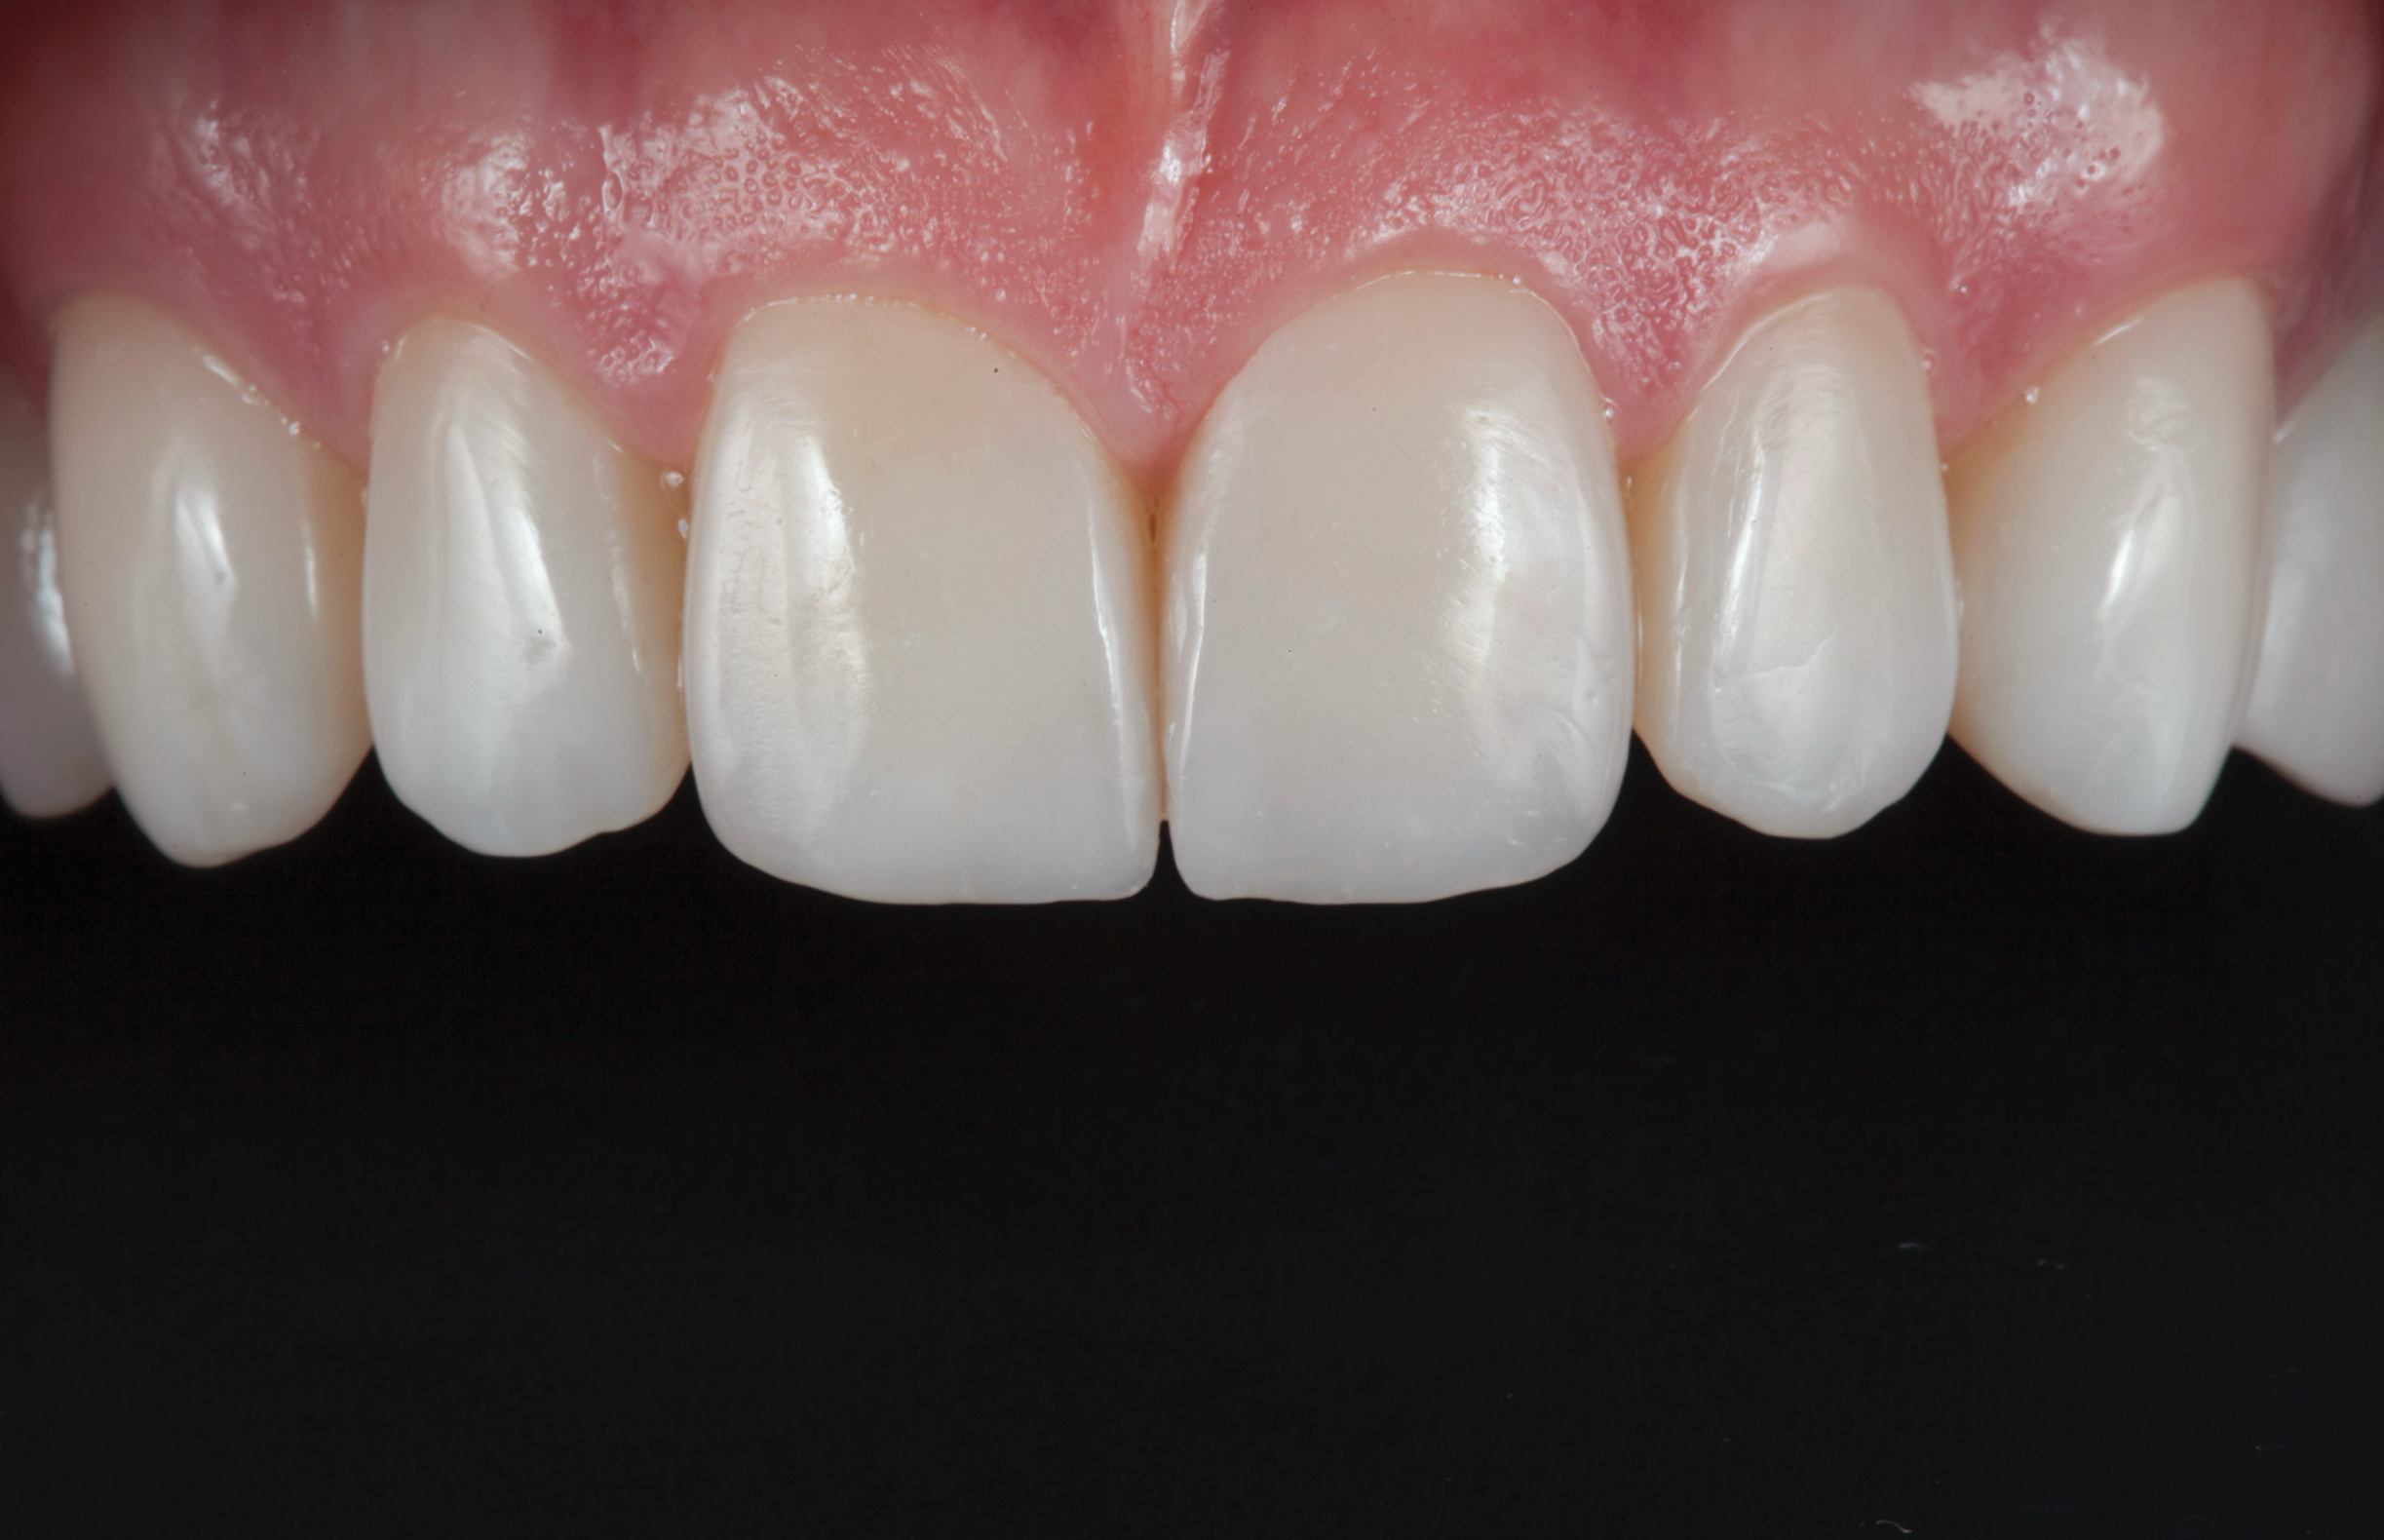

(11.) Postoperative retracted view.

Figure 11

After the composite veneers were finalized, impressions were taken for a monolithic lithium disilicate crown on tooth No. 12. This was placed during a subsequent appointment, and occlusal equilibration was carried out. The patient returned for final photographs a couple of weeks later (Figure 10 through Figure 14).